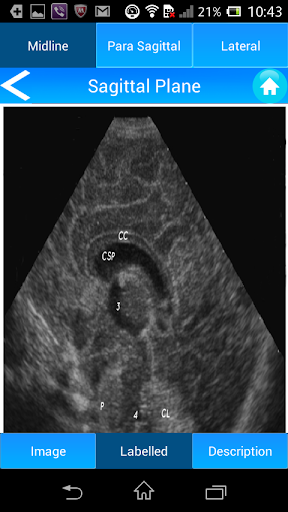

View Window: Aimed at familiarizing Neonatologists with basic Neurosonographic views such as coronal Plane (with six basic standard views at this plane), Sagittal plane (with three standard views at this plane) and other supplementary view windows including Posterior Fontanelle and Mastoid window.

Anatomical Orientation: Image illustration to help identify and clarify sonographic anatomy.